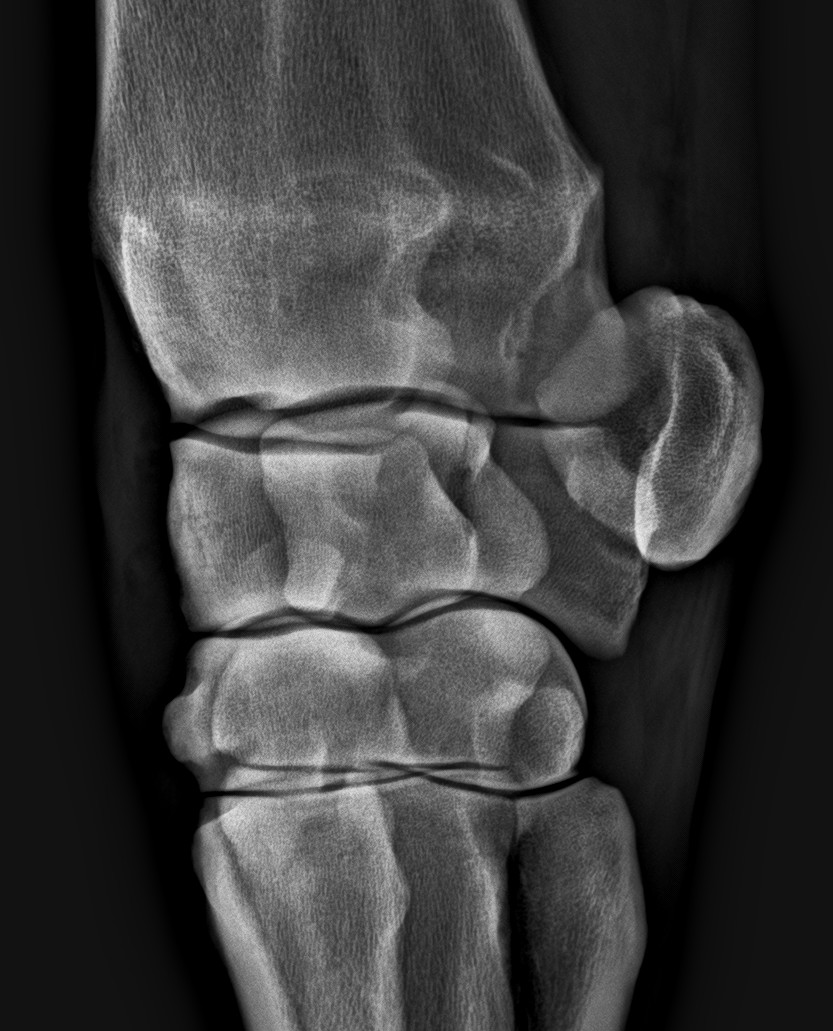

A legszebb ízület

A diagnózishoz a hajlítási próba-érzéstelenítés-röntgen útvonalon juthatunk el. Az ízületbe adott injekciók mellett sokszor szükséges lehet artroszkópiára is.